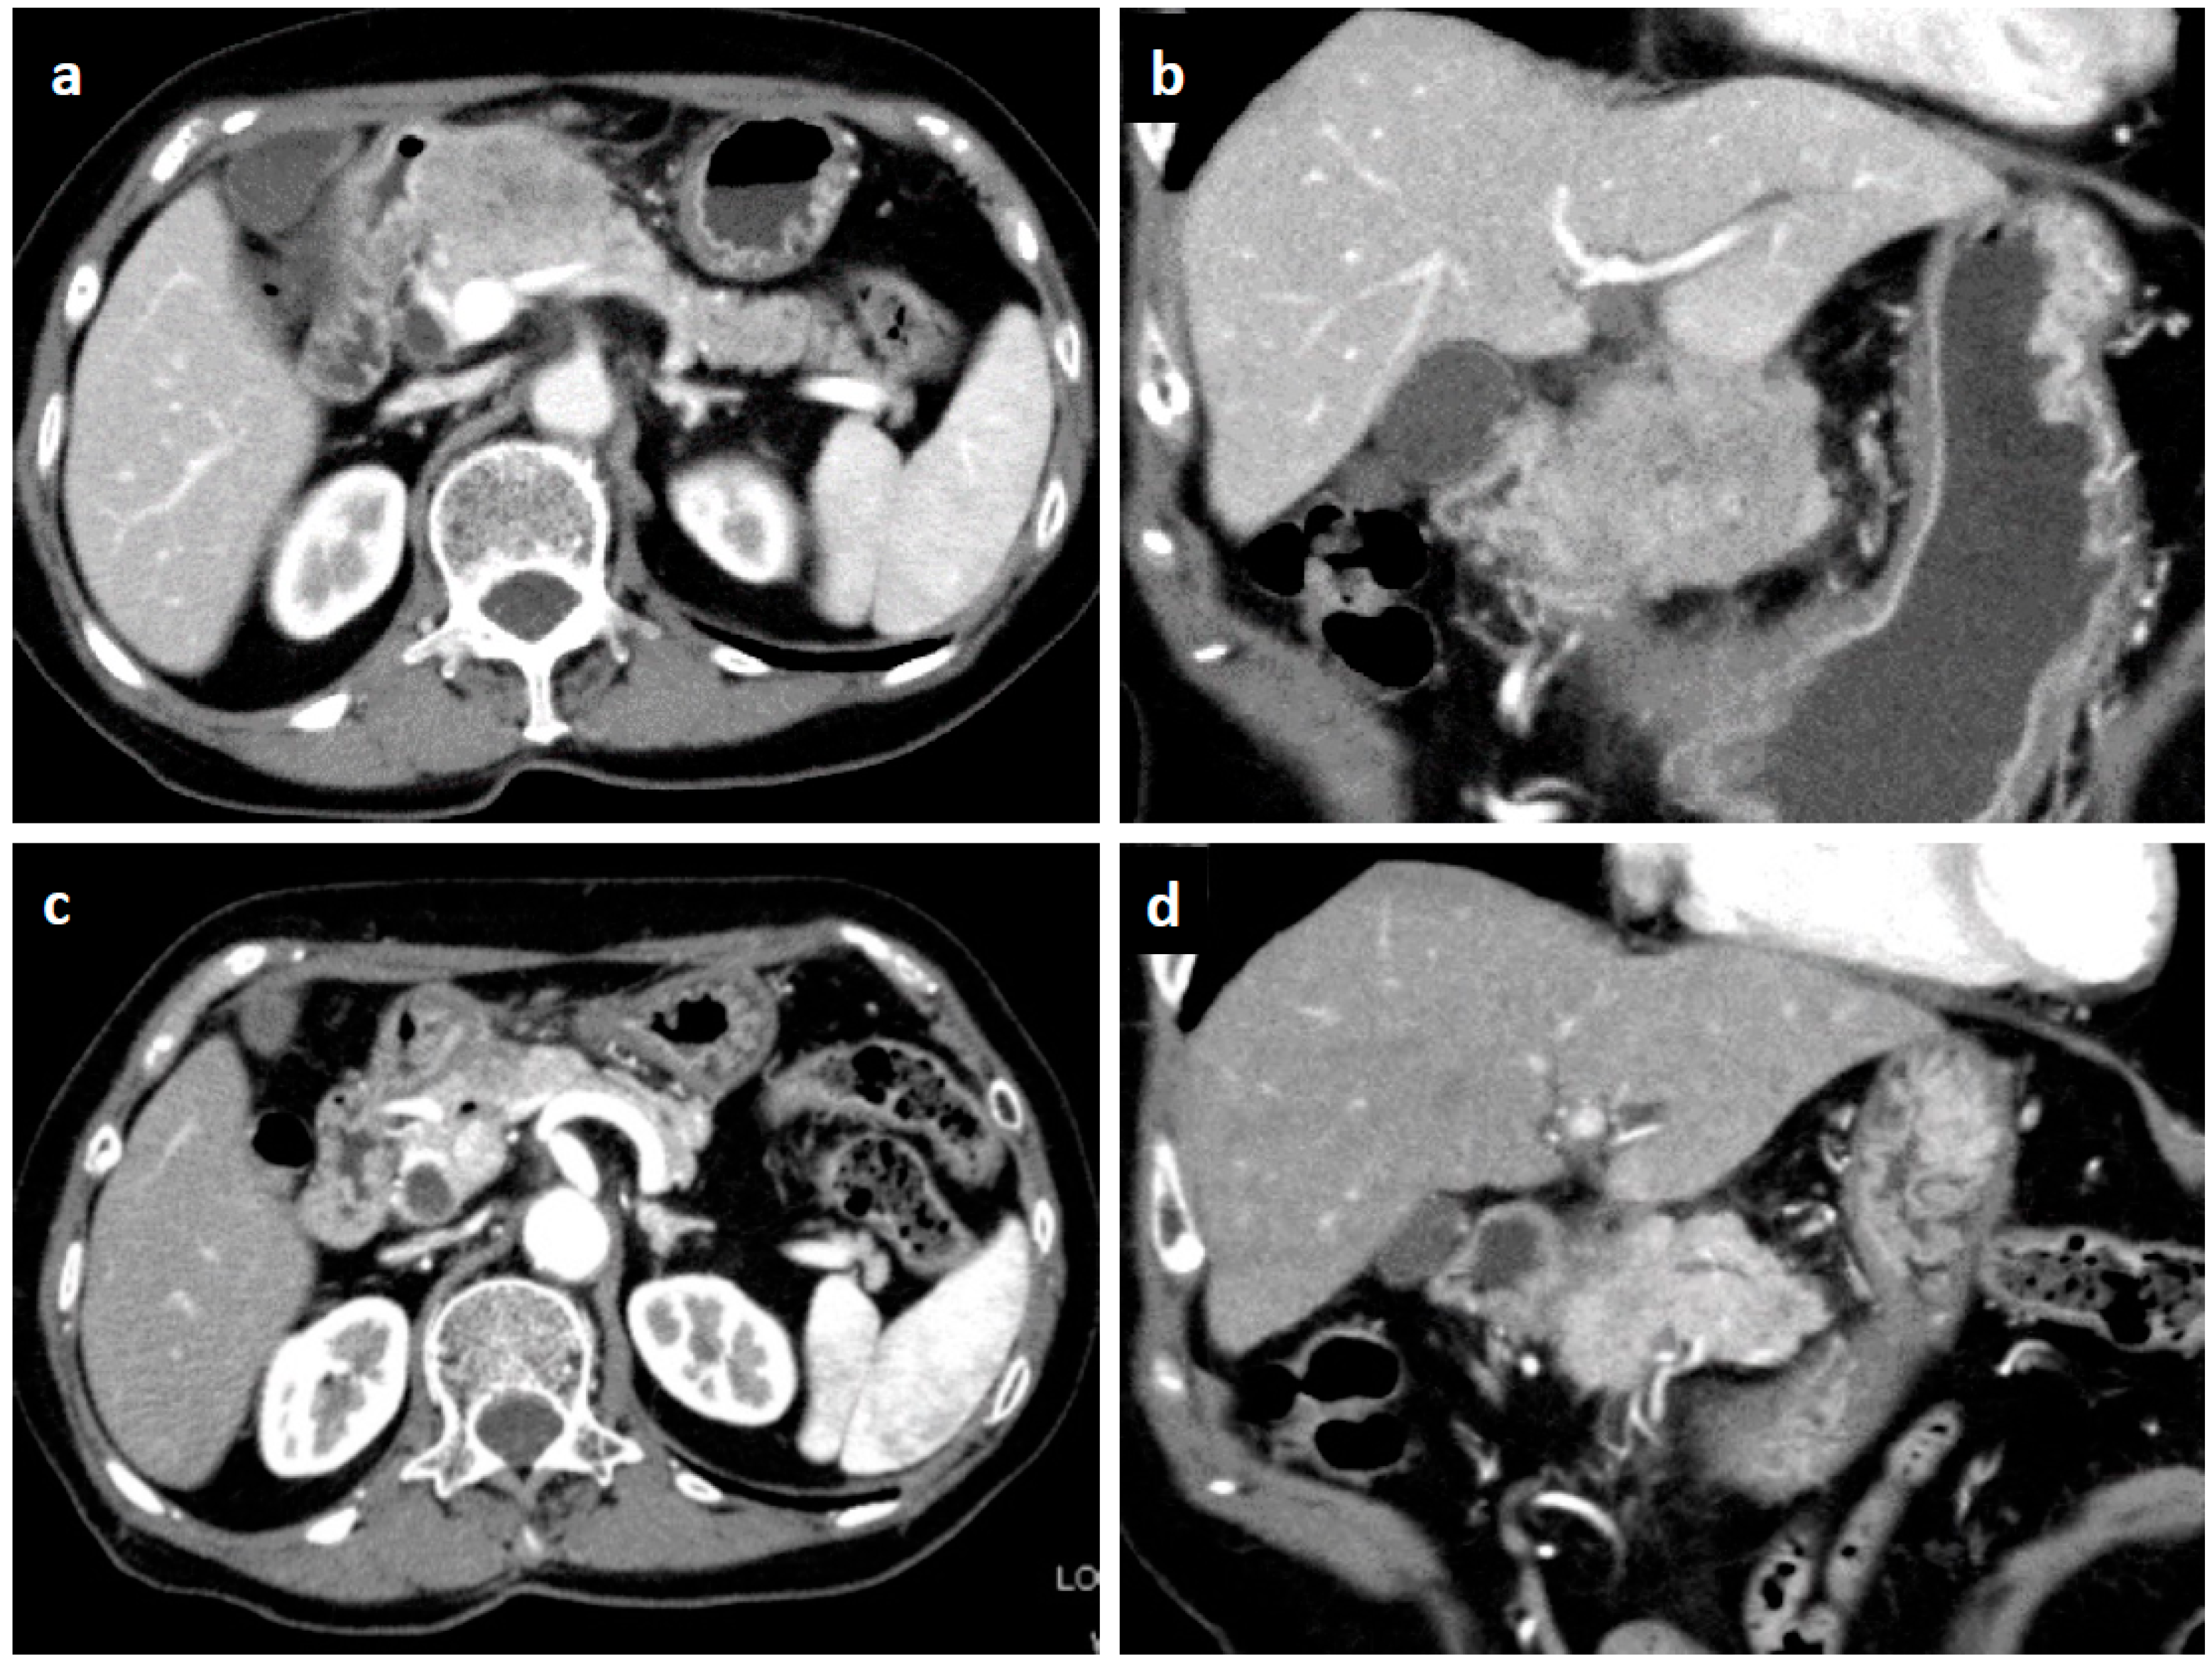

Figure 1.

Enhanced computed tomography. An irregular-margined, low-attenuated mass 5 cm in size was seen at the pancreas head (horizontal view (a), coronal view (b)). One month after the histological diagnosis, the pancreatic mass was markedly shrunken spontaneously (horizontal view (c), coronal view (d)).

Ten days after FNAB, positron emission tomography showed abnormal 18F-fluorodeoxyglucose uptake (SUVmax: 6.95); however, the pancreatic lesion seemed to have shrunk to 2.5 cm in size (Figure 5). Magnetic resonance imaging (MRI) demonstrated an obviously minimized tumorous lesion at the pancreas head (Figure 6). The mass lesion was visible as an iso-intensity signal in a T1-weighted image and as a faintly low-intensity signal in a T2-weighted image, while it was ill enhanced in an EOB image and the signal was heterogeneously repressed in a diffusion-weighted image. A subsequent CT, conducted one month after the FNAB, revealed further minimization of the pancreatic mass (Figure 1c,d). The images obtained in the next two months showed that the tumor had almost vanished. The tumor was no longer visible at the sixth month. During the post-diagnosis course, no medication was administered other than regularly taken hypotensive drugs. A written informed consent was obtained from the patient.